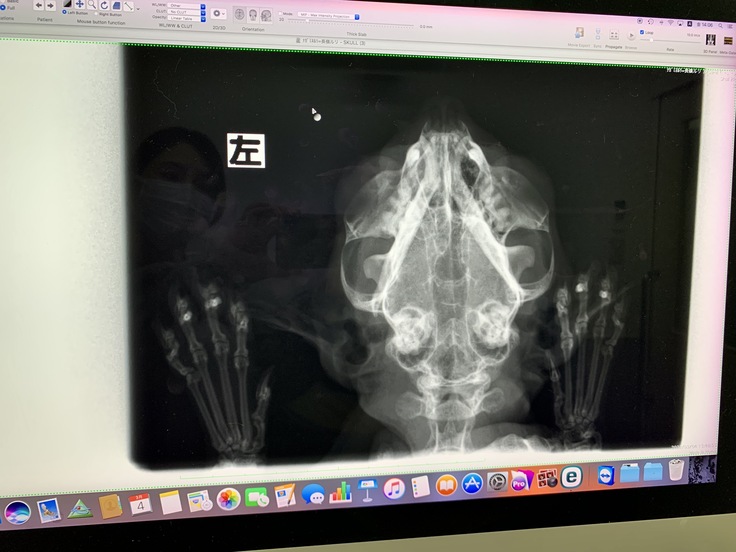

つい先日改めて専門医にレントゲン撮影をしてもらったところ、

「左鼻腔内に白い影が写っています。片方の鼻からしか出血してないこと、

これまでの治療の経過をみる限り腫瘍があることが強く疑われます。」

と言われました。

▼3/4 鼻血が出たのは初めてだったので、病院が休診日だったのもあり、以前先住猫を診てもらっていた別の専門医に掛かりました。病院設備的に出来る事としてレントゲンをしてもらいました。結果、左鼻腔内一部の透過性が悪く、鼻腔内に腫瘍がある疑いが強いとのことでした。

処方・レントゲン検査

▼3/9 食欲がほとんどないのと水を飲んでいる姿をいつもより見かけないので、朝から最初に診察してもらった近所の病院に行きました。他院のレントゲン写真をみてもらい、こちらの先生も同じ見解でした。やはり確定診断のためのCT,MRIによる検査が治療には必要とのこと。

▼3/16 紹介されたCT・MRI設備の整った別の病院へ精密検査に行きました。画像診断の結果、血餅や鼻づまりではなく、腫瘍であろうとのことでした。範囲がひろがっていて、眼球を圧迫し、上顎喉の方にも進んでいるとの見解でした。受け取った検査資料を元の病院へ届ける予定です。 ※レシートしかないのはショックで明細書を受け取り忘れてしまったので、後日郵送にて届く予定です。届き次第載せる予定です。